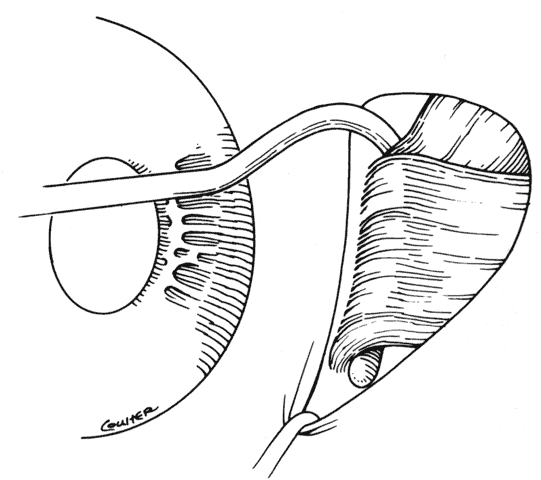

Reintervention to correct strabismus is indicated if a technical problem occurred immediately after the initial procedure. A muscle that has become disinserted or is “lost” postoperatively requires immediate exploration and correction of the problem (Figs. 2 and 3). A similar situation may occur when a previously operated muscle retracts ("slips") inside the muscle capsule (Fig. 4). The slipped muscle will appear paretic, and early surgical intervention should be considered. The clinical pictures of these technical failures are very similar. There is poor function of the affected rectus muscle, and the induced strabismus will be noncomitant. Operations may be performed on the incorrect eye muscles or eye (Fig. 5). If this occurs, reoperation should not be delayed.

Fig. 3. This diagram demonstrates the findings of surgical exploration of the patient in Figure 2.

Fig. 4. Failure to incorporate a portion or the entire tendon of the muscle when sutures are placed near the insertion can permit a portion or all of the muscle to slip posteriorly and produce an exaggerated recession effect. On exploration, the muscle capsule will be present but the tendon will be retracted within the muscle capsule.